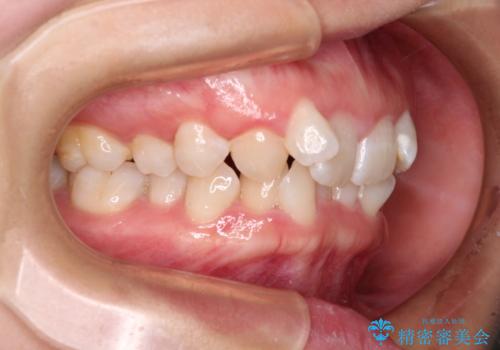

口元の突出感がない分、奥歯を前方に移動させる必要がありましたが、予定の2年間で無事に治療を終えることができました。